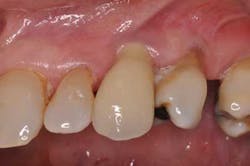

The patient returns for a two-week follow-up and the gingival erythema is absent. Oral hygiene instruction is reviewed as there is still visible plaque on the adjacent teeth. Probing of the implant reveals no bleeding, thus the peri-implant mucositis appears to have been successfully treated.

Fig. 9: Two weeks after initial presentation, peri-implant mucositis appears to have subsided.